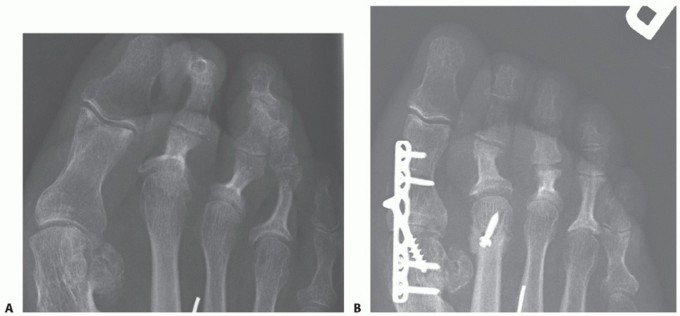

- FIG 2 • A,B. The Weil osteotomy can be used to shorten the second metatarsal as well as to decrease the overall prominence of the second metatarsal head.

The Weil osteotomy can be used to shorten the second metatarsal as well as to decrease the overall prominence of the second metatarsal head (FIG 2).

This procedure is used for persistent subluxation of the second MTP joint after adequate soft tissue procedures have been performed.

It may be used as an alternative to a flexor to extensor transfer.

A flexor to extensor transfer can be performed simultaneously for additional correction in refractory cases.

- TECH FIG 6 • A. Diagram of osteotomy plane, made using an oscillating saw. Care must be taken to initiate the saw cut at the dorsal most aspect of the second metatarsal head. B. The osteotomy is slid proximally and fixed with a compression screw from dorsal to plantar. (continued)

With use of an oscillating saw, a cut is initiated at the articular surface of the most dorsal aspect of the

second metatarsal head.

The cut is carried proximally and parallel to the plantar plane of the foot (TECH FIG 6A).

The plantar osteotomy fragment is then grasped with a pointed reduction clamp and slid proximally to achieve the desired amount of shortening (TECH FIG 6B).

The osteotomy is finally secured with a compression screw placed in lag fashion from dorsal to plantar (TECH FIG 6C).

The excess dorsal bony prominence is shaved to a smooth surface.